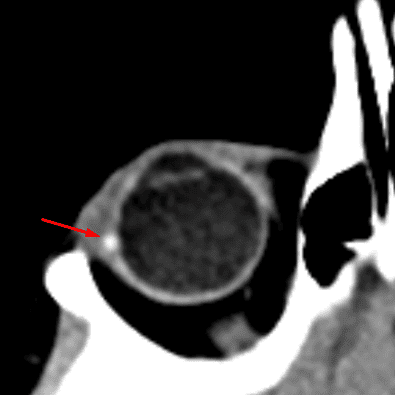

Optic Disc Drusen

Case 14